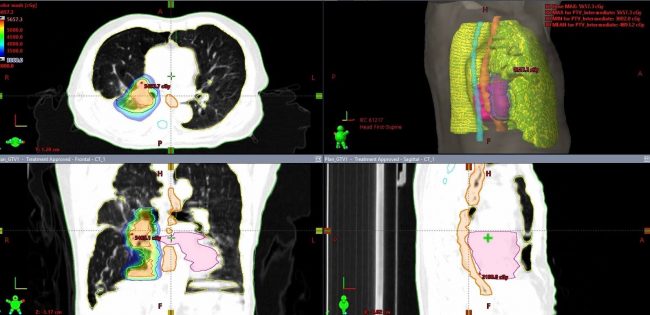

En el caso de esta semana tuvimos a un niño de 11 años, quien tenía más de dos meses con dolor de cabeza. Se le diagnosticó un tumor de la región pineal sin inflamación. El caso tratado por nuestro equipo médico el Dr. Eduardo Lovo y el Dr. Víctor Caceros apoyados por los técnicos y nuestro físico médico, el Lic. William Reyes. Realizamos radiocirugía con nuestra máquina bisturí rayos gamma para tratarlo. La expectativa de curación es mayor al 95% de probabilidad sin ninguna efecto secundario.